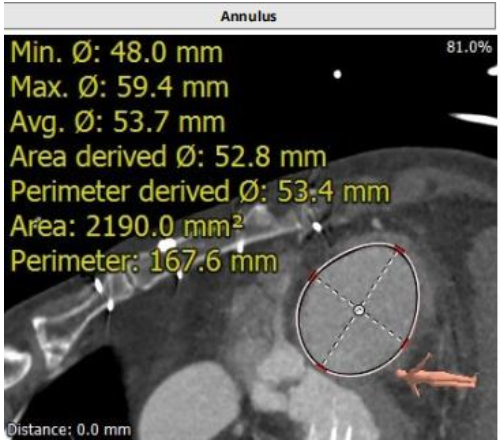

三尖瓣影像评估

瓣环周长167.6mm,平均周长径53.4mm

低位右房周长246.0mm,平均周长径78.3mm

上腔静脉入路水平夹角约为92°

三尖瓣瓣环与室间隔夹角约为97°

室间隔水平夹角约为30°

颈静脉入路水平夹角约为30°